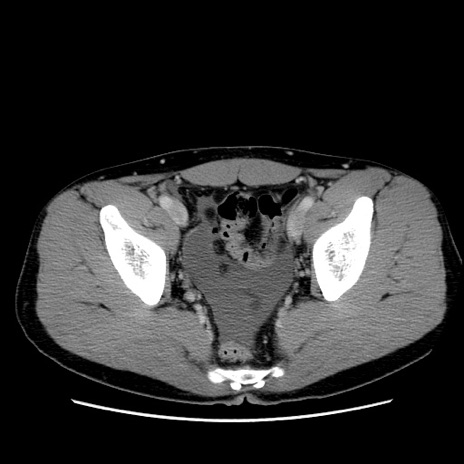

症例36(横断像)

【症例】20歳代 男性

【主訴】心窩部痛

【現病歴】今朝より上腹部痛あり。一旦軽快していたが再度出現したため救急要請。昨日夕に白身の魚を含む刺身を食べた。

【身体所見】BP 136/89mmHg、HR 74/min、BT 37.0℃、腹部:膨満、軟、心窩部に圧痛あり。反跳痛なし、筋性防御なし、腸雑音やや亢進あり。

【データ】WBC 17700、CRP 0.48